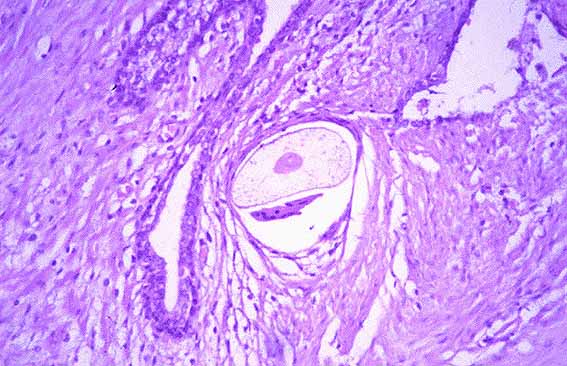

Fig 1.- Reacción granulomatosa con presencia de una célula gigante multinucleada rodeando la vaina de un pelo en el estroma prostático. (H&E, 100x).

. Fig 2.- Reacción granulomatosa con presencia de una célula gigante multinucleada rodeando la vaina de un pelo en el estroma prostático. (H&E, 200x).